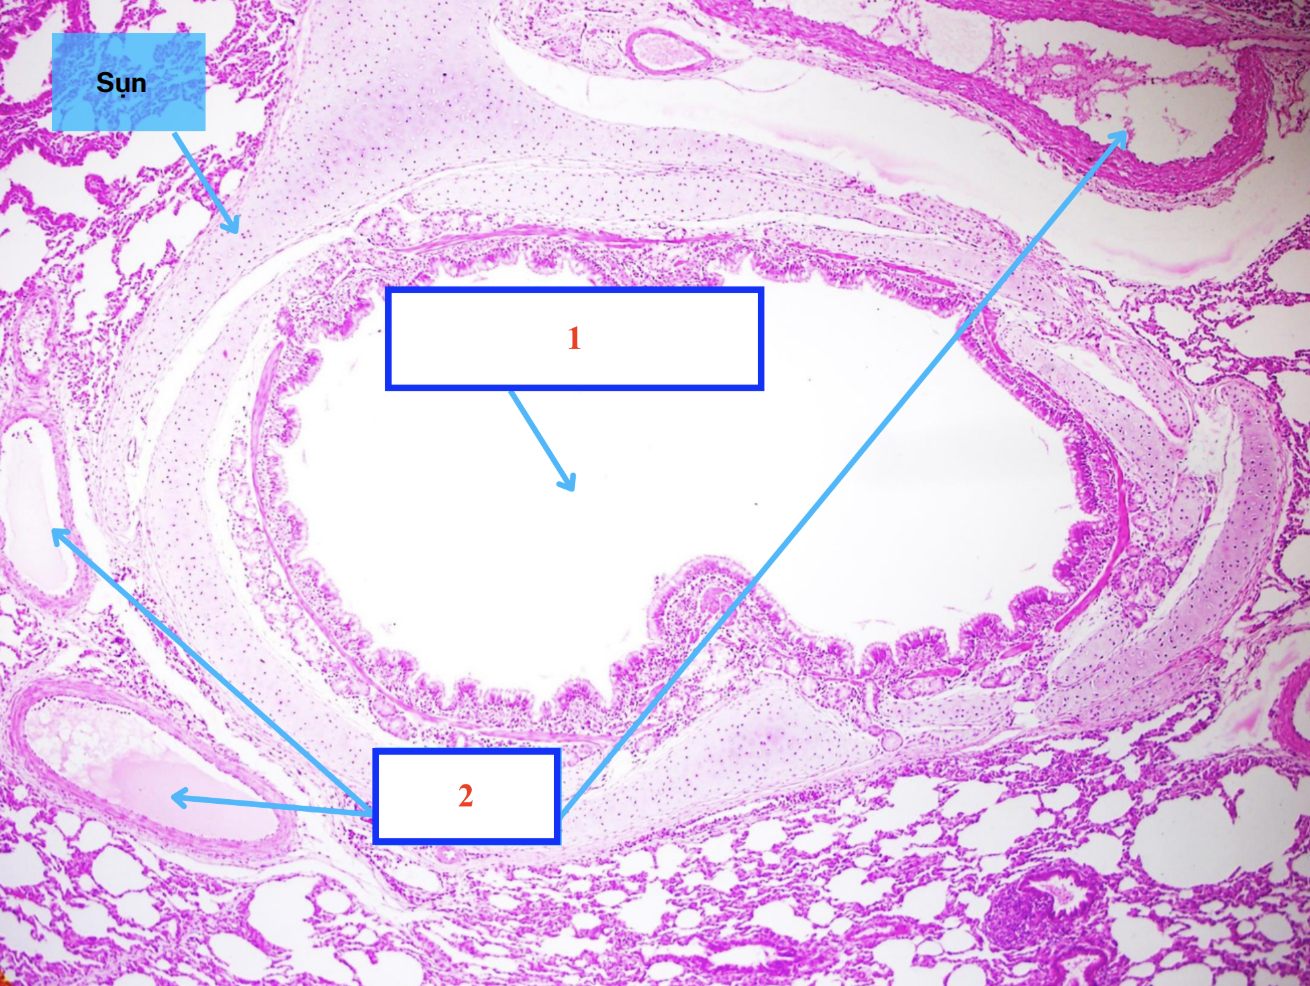

MẠCH MÁU/ ĐỘNG MẠCH:

Lớp áo trong

Lớp áo giữa

Lớp áo ngoài

Màng chun trong

Màng chun ngoài

Cấu trúc gì ?

Số 4 là tế bào gì ?

Lớp áo trong - mạch máu

Lớp áo giữa - mạch máu

Lớp áo ngoài - mạch máu

Tế bào nội mô